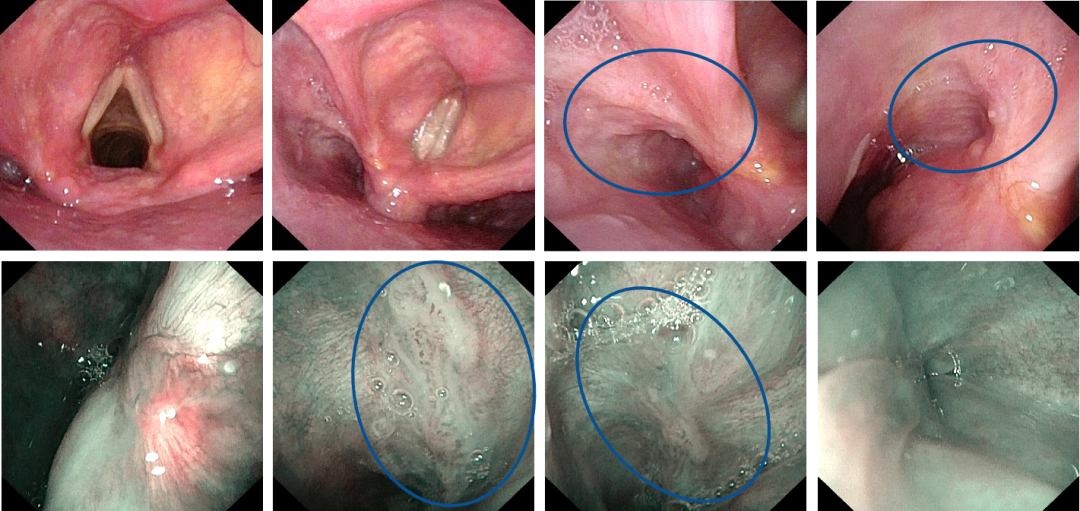

术前电子喉镜检查(病变局限在梨状窝内侧壁和前壁)

图片

术后一年复查